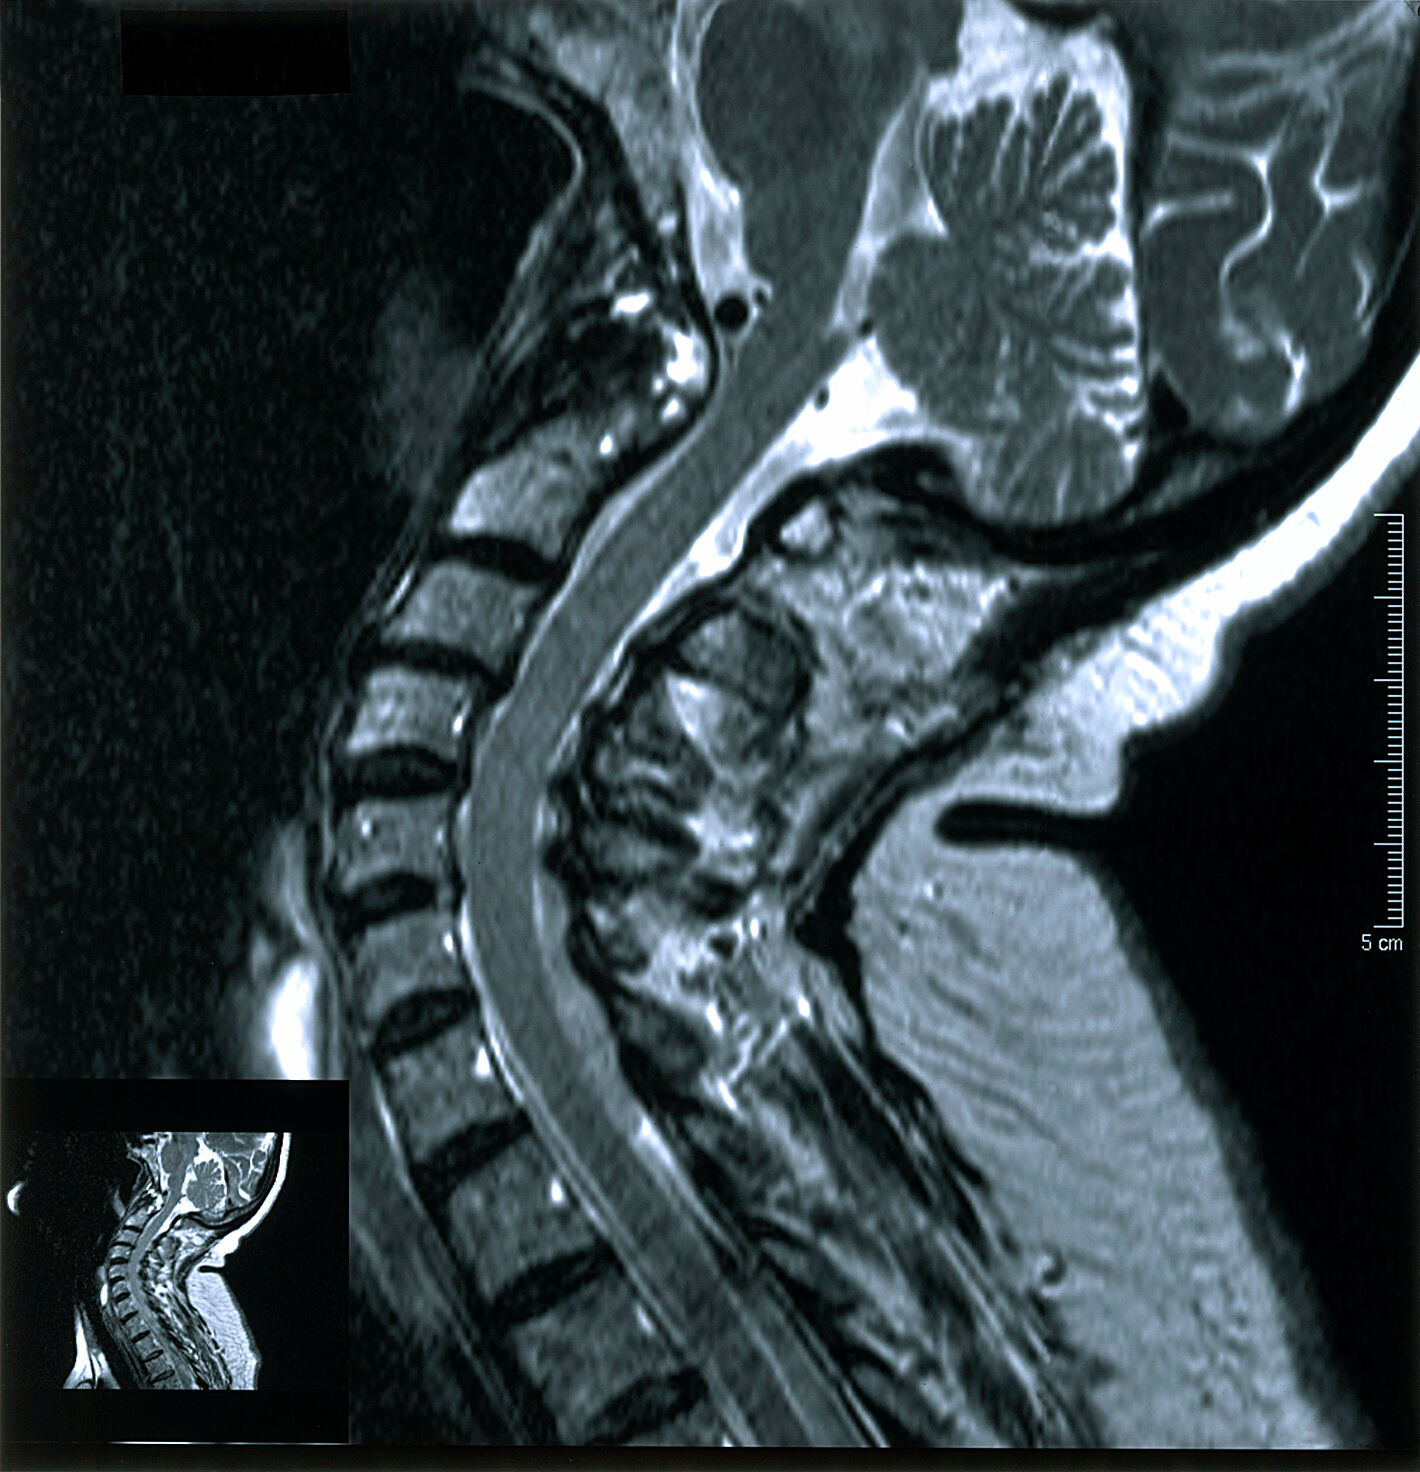

From www.slideshare.net

MRI in neck imaging Arthritis In Neck Mri It also explores the various. if your doctor suspects you have a type of arthritis, such as osteoarthritis, he or she may use a magnetic resonance imaging (mri). The discs may naturally dry. Healthcare providers sometimes call it. the article describes the symptoms, causes, and diagnosis of neck arthritis. Spondylosis is when parts of your spine begin to. Arthritis In Neck Mri.

MRI in neck imaging Arthritis In Neck Mri The discs may naturally dry. if your doctor suspects you have a type of arthritis, such as osteoarthritis, he or she may use a magnetic resonance imaging (mri). cervical refers to seven stacked bones (vertebrae) in your neck. Healthcare providers sometimes call it. the article describes the symptoms, causes, and diagnosis of neck arthritis. Two of the. Arthritis In Neck Mri.